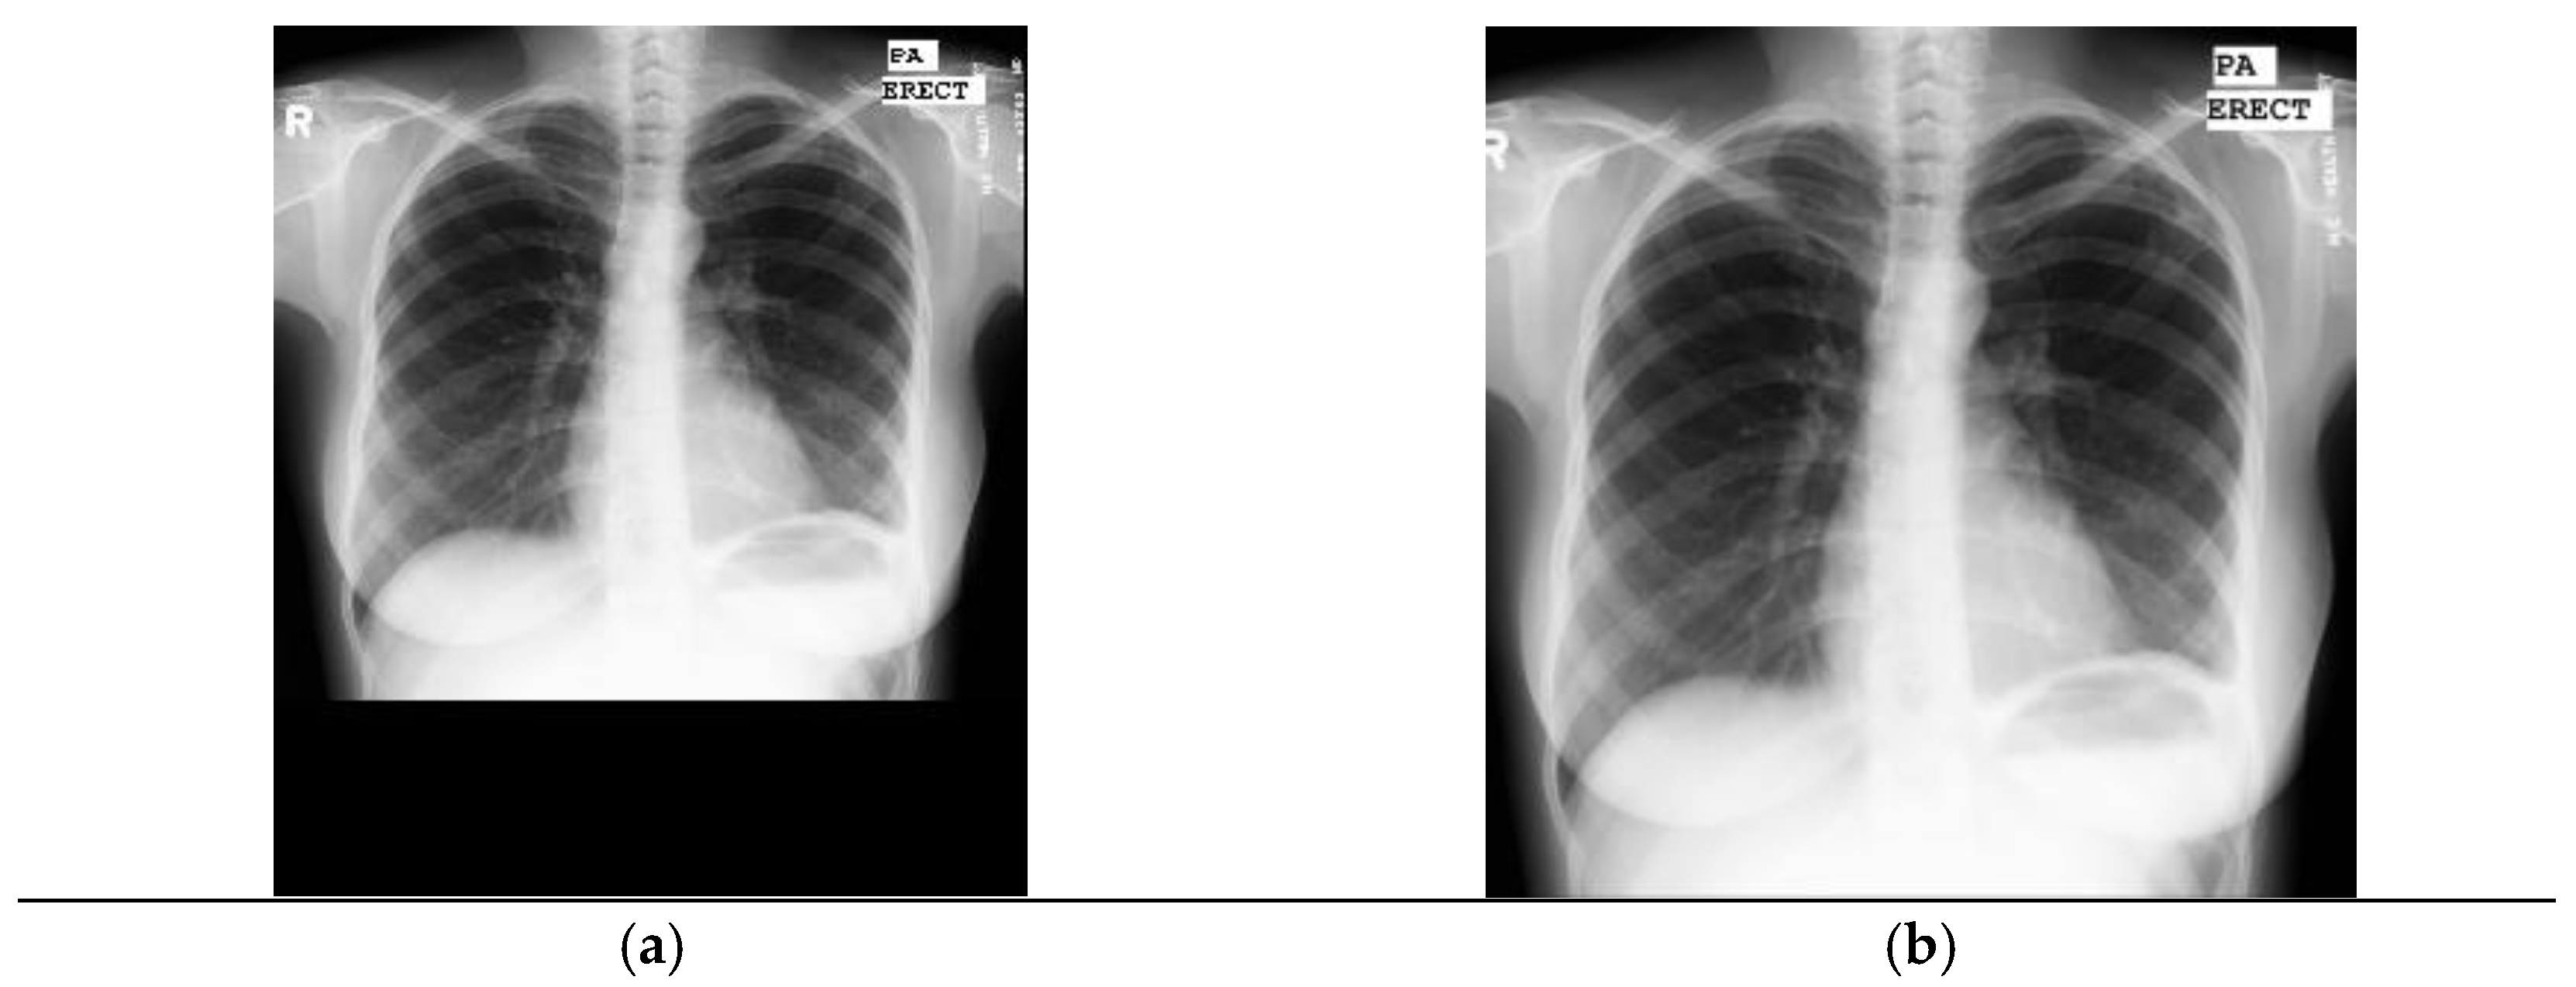

2.1.1. Tuberculosis Dataset

Tuberculosis Montgomery County Dataset